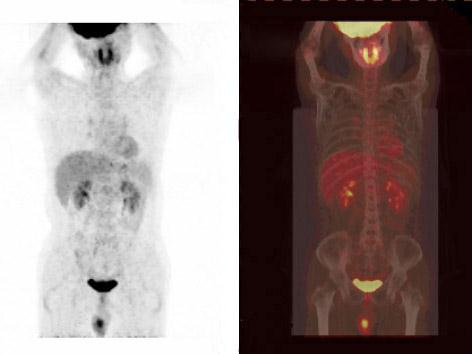

问题 高度怀疑睾丸恶性肿瘤,不宜进行的检查是 ( )

选项 A、CT B、睾丸穿刺活检 C、AFP和HCG测定 D、B超 E、MRI

答案 B